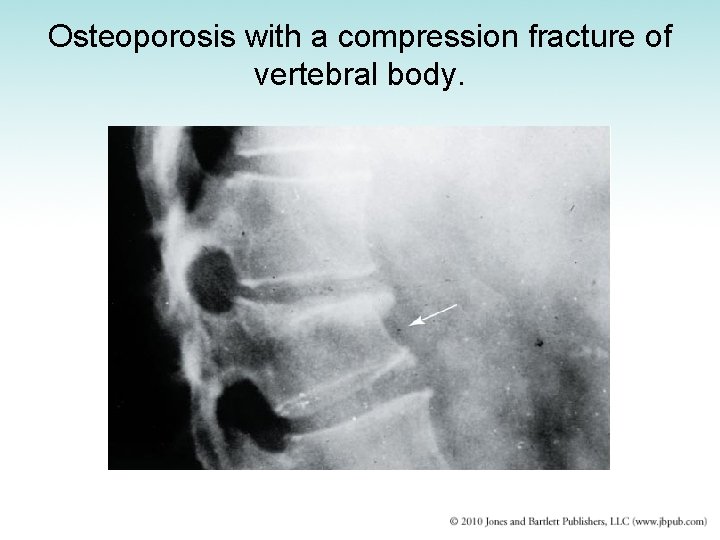

Osteoporosis with a compression fracture of vertebral body.

Osteoporosis • Generalized thinning and demineralization of entire skeletal system – “Porous bones” – Most common in postmenopausal women – Loss of estrogen accelerates rate of bone resorption – Also develops in elderly men • Treatment: high-calcium diet, estrogen

Osteoporosis, with compression fracture of vertebral body